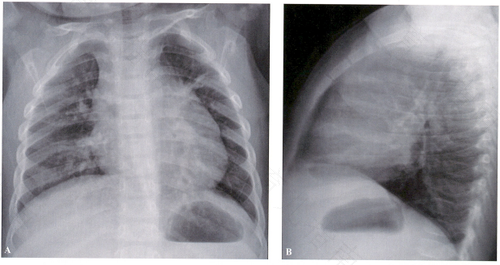

胸壁结核是会传染的一个疾病,通常情况下会依靠飞沫传染,绝大多数胸壁结核为继发性感染,常见的就是肺结核,它是能够传染的疾病,如果不小心将患者咳出的涂抹吸入到肺部,那么就会感染这个疾病,所以它是会传染的疾病。